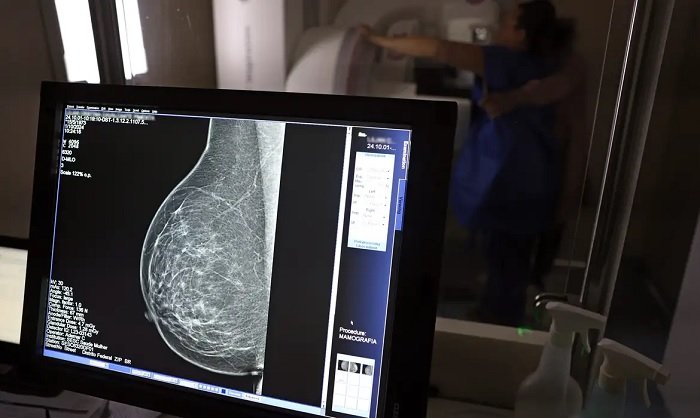

O Ministério da Saúde passou a recomendar o acesso a mamografia, via Sistema Único de Saúde (SUS), para mulheres de 40 a 49 anos – mesmo que não haja sinais ou sintomas de câncer de mama. De acordo com a pasta, a faixa etária concentra 23% dos casos da doença, e a detecção precoce aumenta as chances de cura.

Até então, a orientação era que o exame fosse feito a partir dos 50 anos.

A medida faz parte de um conjunto de ações anunciadas nesta terça-feira (23) voltado para a melhoria do diagnóstico e da assistência. A recomendação para mulheres a partir dos 40 anos é que o exame seja feito sob demanda, em decisão conjunta com o profissional de saúde. (Foto: José Cruz/Agência Brasil)